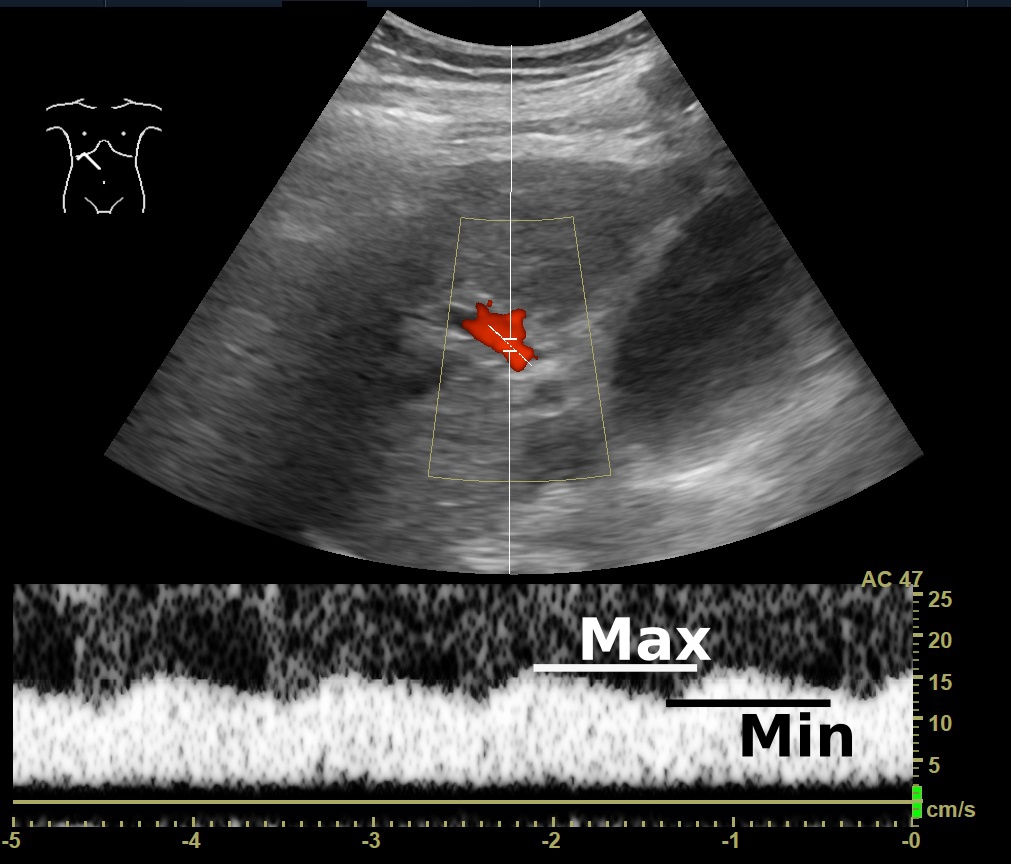

도플러 초음파 검사로 5초 동안 측정한 문맥의 혈류 속도이며, '''최대''' 속도와 '''최소''' 속도를 보여준다.

문맥의 박동성은 도플러 초음파 검사로 측정할 수 있다. 박동성 증가는 간경변뿐만 아니라 우심방 압력 증가(이는 차례로 우측 심부전 또는 삼첨판 역류에 의해 발생할 수 있음)에 의해 발생할 수 있다.[11] 문맥 박동성은 박동 지수(PI)로 정량화할 수 있으며, 특정 컷오프 이상의 지수는 병리학적 상태를 나타낸다.